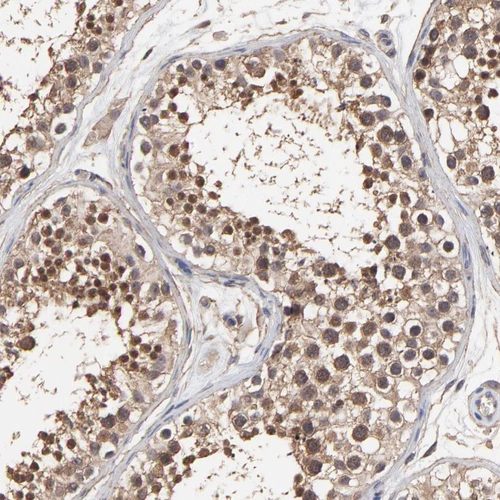

Immunohistochemical staining of human testis shows moderate nuclear and cytoplasmic positivity in cells in seminiferous ducts.